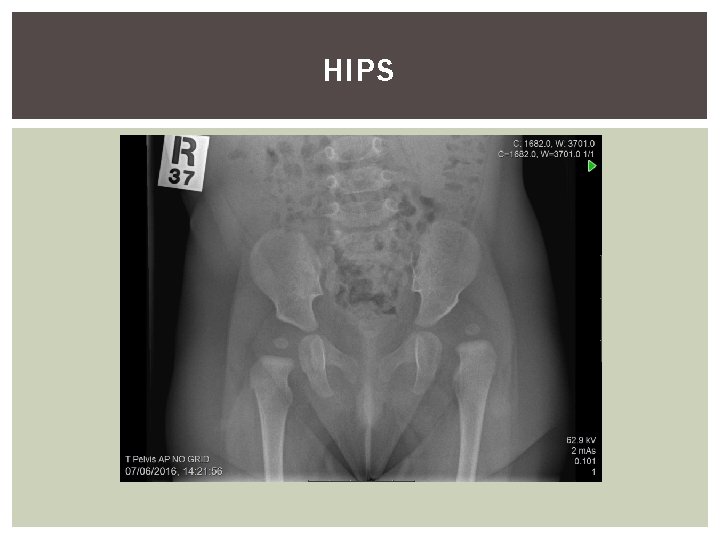

HIPS

THE HIP NB children are poor locators of pain, and hip pain is often referred to the knee! Complete hip ax for all children complaining of knee pain.

ABNORMAL HIP MOTION THINGS TO WATCH OUT FOR 1. DDH 2. PERTHES DISEASE 3. SCFE

PATHOLOGIES TO CONSIDER Infants and toddlers § Hip dysplasia § Neuromuscular disease -Cerebral palsy Toddlers § Legg-Calve-Perthes disease Pre-teens § Legg-Calve-Perthes disease § Slipped Capital femoral epiphysis